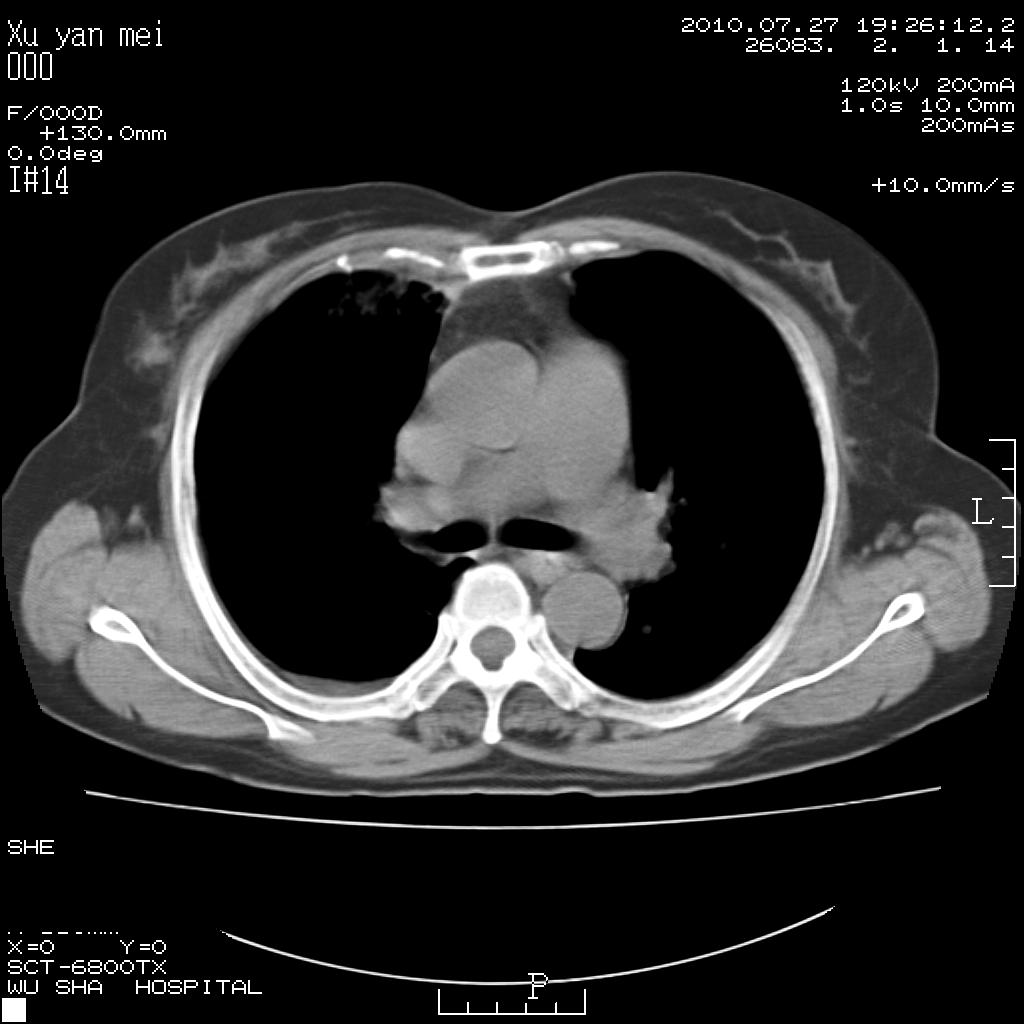

女,60岁,胸痛就诊,右肺结核?炎症?其它?(胸片右侧中上肺野确实看不到什么啊)

1)考虑两肺感染性病变;建议抗炎治疗后复查。2)双侧少量胸腔积液。

1)考虑两肺感染性病变;建议抗炎治疗后复查。2)右侧少量胸腔积液。

双肺炎症可能性大,建议抗炎后复查。右侧胸腔少量积液。双侧胸膜轻度增厚。